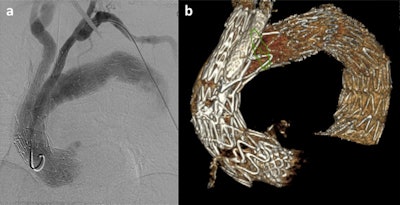

The hospital's first 3D-printed aorta was produced in 2019, and it was for a patient with an aortic iliac aneurysm. Following preoperative CT angiography, the surgical team sized the endograft and prepared the fusion mask for intraprocedural guidance, and then extracted the DICOM file of the aorta and converted it into an STL file, which is a format native to the stereolithography CAD software created by 3D systems. From this file, the model was printed. The first simulation was deemed similar to a classic procedure and much better than commercially available endovascular simulators, according to Haulon.

The printed models comprise three layers for strength and versatility, and the print needs to also include connectors. Weak points are strengthened by reinforcing balls to ensure no leakage.

Such models look and act just like real aneurysms, and each can serve as practice for 50 to 100 cases, Haulon told attendees, pointing out that the models have the same size aorta as the specific patient, the same pathology to the millimeter and simulated blood flow from the pulsatile pump.